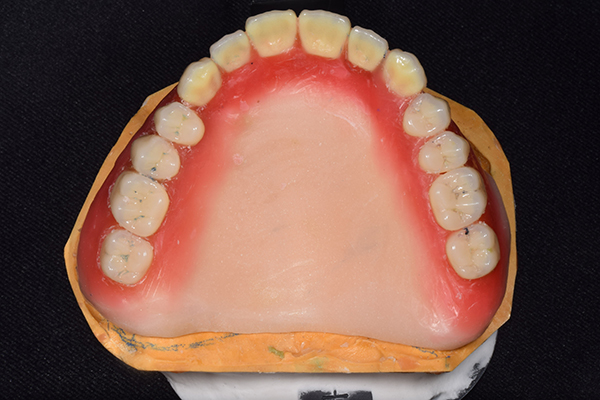

入れ歯は極力薄くするために金属を使用しました。しっかり噛める様にするため、ノンメタルクラスプデンチャーにはしませんでした。

上の入れ歯(表)

上の入れ歯(裏)

お口に入っている状態です。嘔吐反射が強かったため、うわあごの部分をくり抜いて作っています。

そのためにはしっかり歯に維持力をかける事、歯茎の部分に圧をかけるため、金属をつかって入れ歯を作成しました。